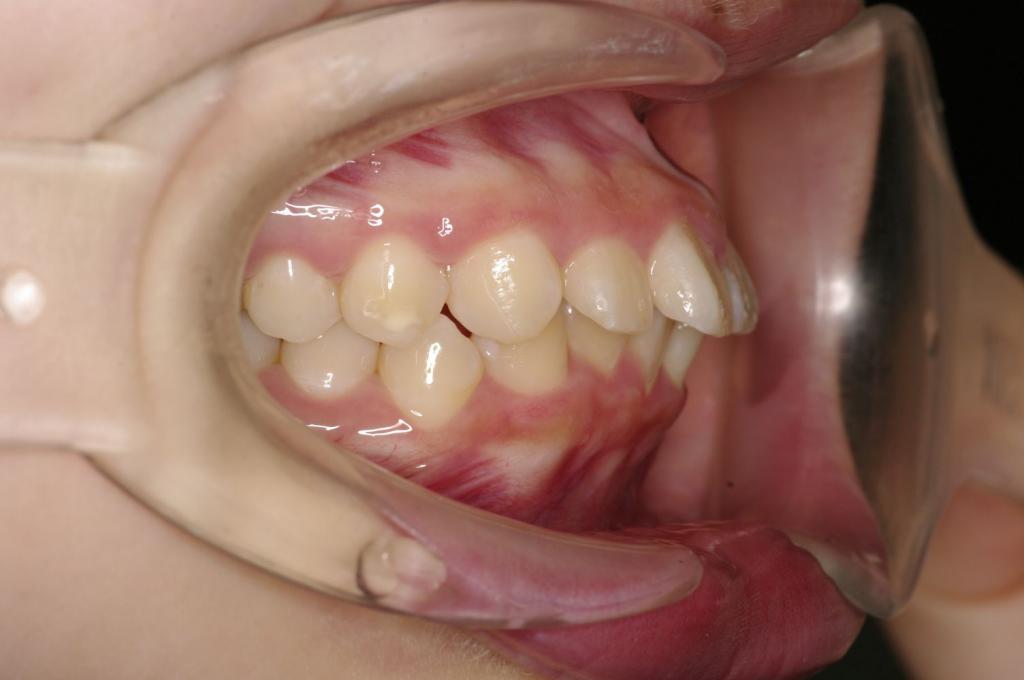

前歯、出っ歯・開咬の矯正治療

(治療期間、治療前後写真、治療方法、費用)WORKS